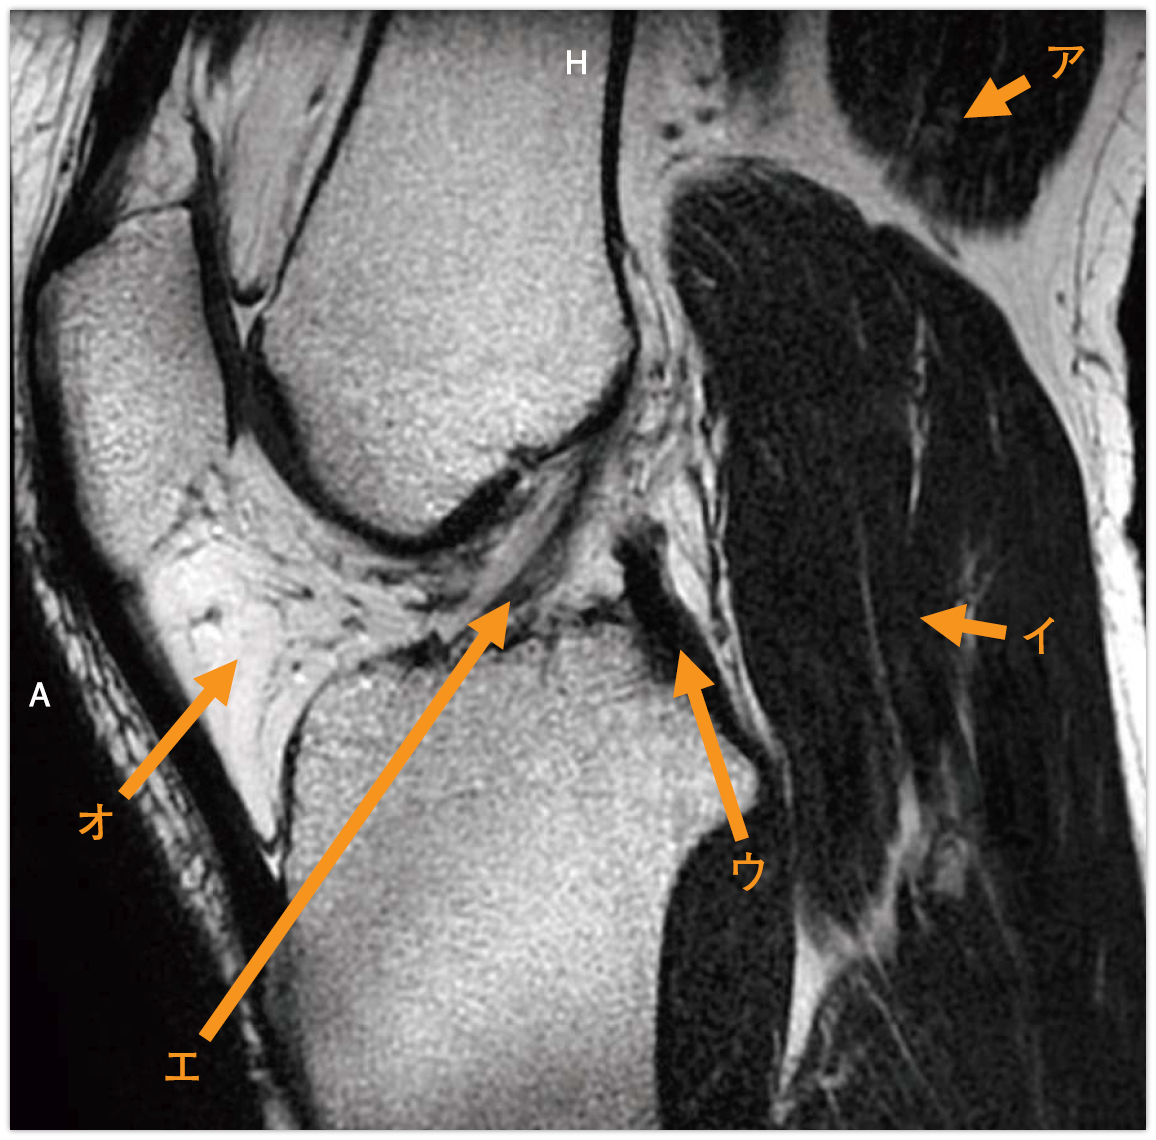

膝関節MR像(別冊No.2)を別に示す。正しい組合せはどれか。

- 1ア

腓腹筋

- 2イ

外側広筋

- 3ウ

内側半月板

- 4エ

前十字靱帯

- 5オ

膝蓋靱帯